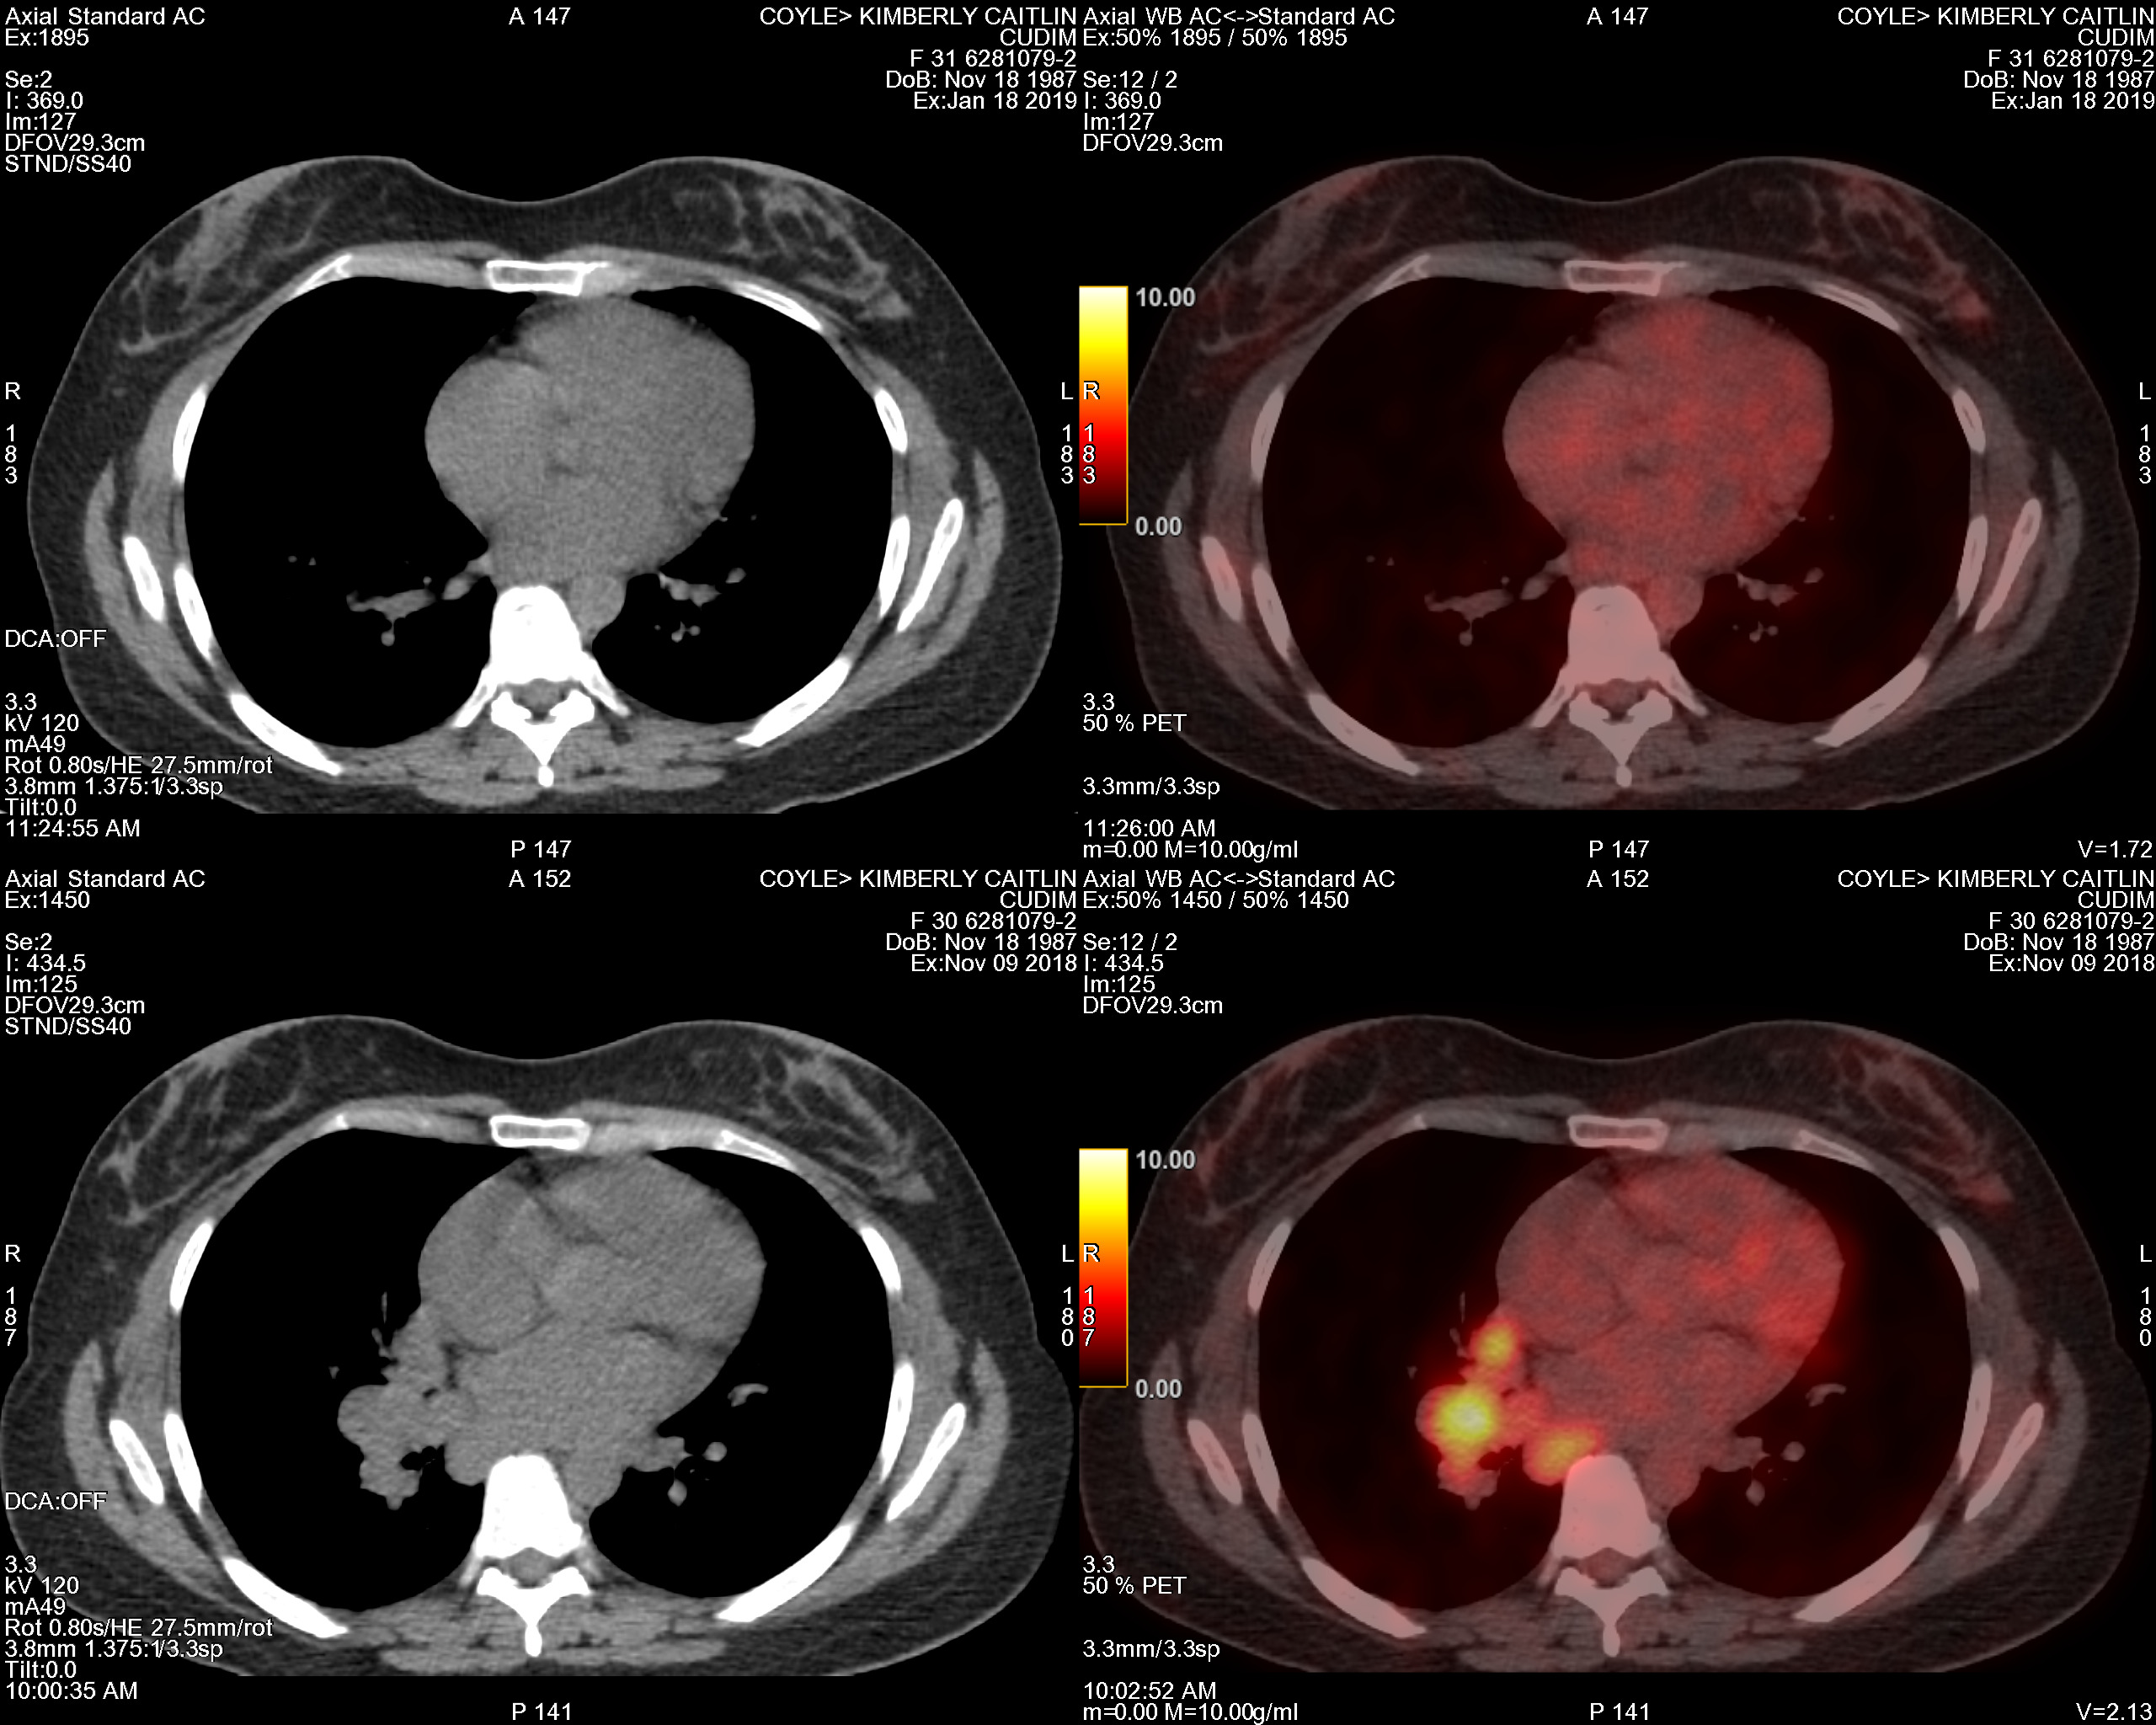

PET Scan Number Two

The Results Are In…Chemo Works

chest

January 23, 2019